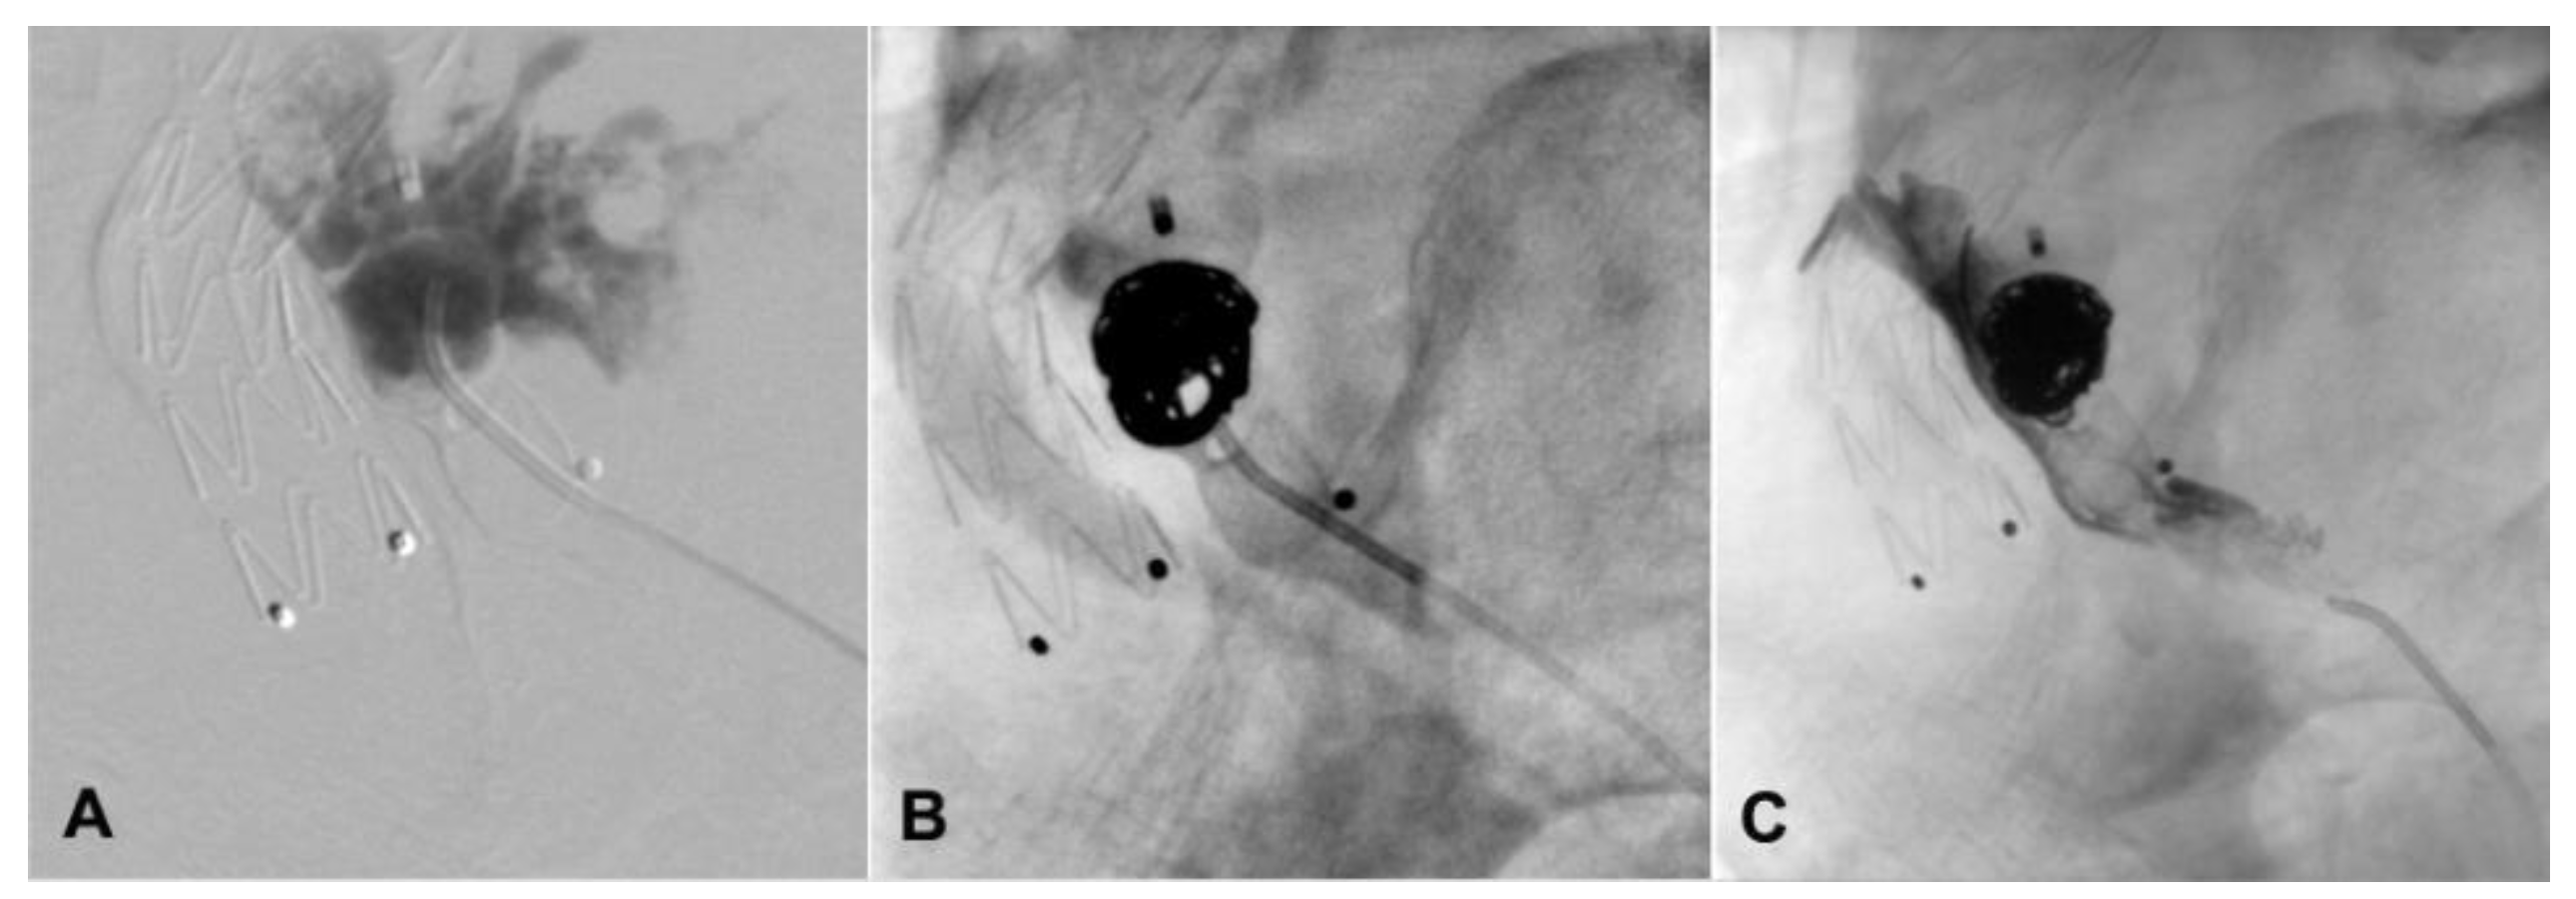

2. Case Presentation